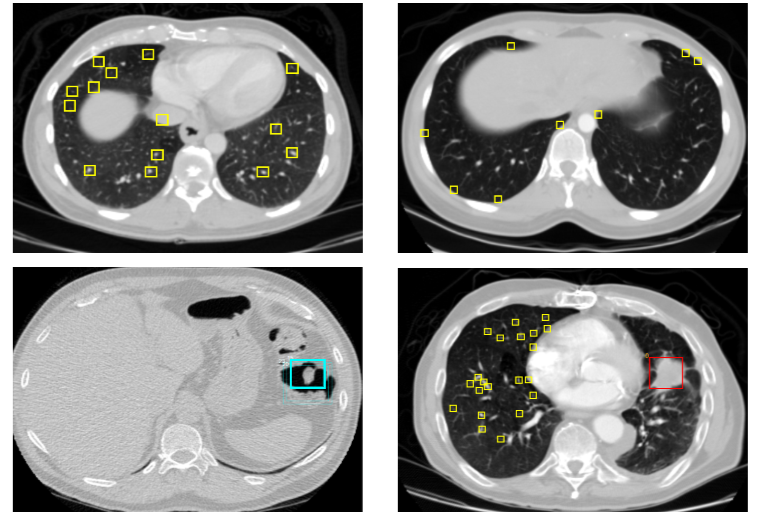

1.2 肿瘤在CT图像中的表现

不同类型的肿瘤在CT图像上表现出不同的特征:

良性肿瘤:通常边界清晰、形态规则、密度均匀

恶性肿瘤:往往边界模糊、形态不规则、密度不均匀,可能伴有周围组织浸润

这些视觉特征为计算机视觉算法提供了分类依据,但也带来了挑战,因为不同肿瘤类型间的差异有时非常细微。